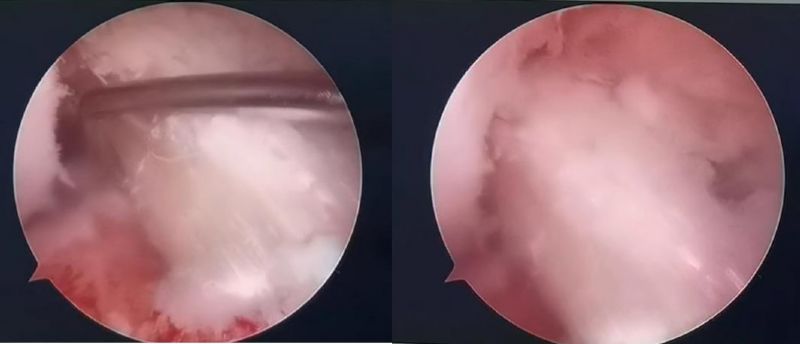

關節鏡下軟骨損傷

經患者同意后,李鵬主任手術團隊制定詳細手術方案。手術如期進行,經團隊密切配合,對幾位患者分別順利完成關節鏡下膝關節鏡鏡檢、關節清理、股薄肌半腱肌取腱移植術、前交叉韌帶重建術、軟骨損傷微骨折術、半月板縫合修整術等。

鏡下重建前交叉韌帶走形、張力良好